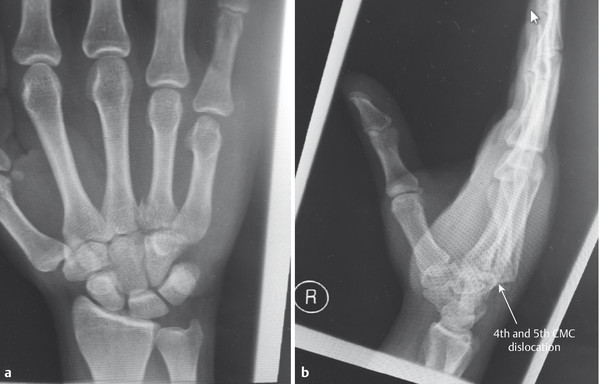

14.5 Fracture Dislocations of the Base of the Fourth and Fifth Metacarpals

These injuries can be easily missed and that is why it is essential to always examine three views (anteroposterior [AP], lateral, oblique) in the emergency department (Fig. 14‑10 a,b). They are inherently unstable and even after reduction under anesthesia the base of the fourth and fifth metacarpal will often re-dislocate even in a well-molded plaster cast.

The best approach is closed reduction and Kirschner wires going into the hamate bone from the fourth and fifth metacarpals (Fig. 14‑11). Rarely, it is necessary to open these fractures to achieve reduction.